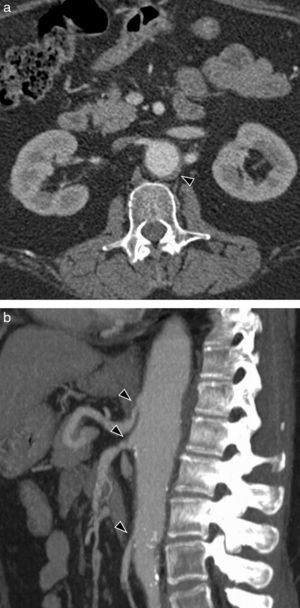

Multidetector computerized tomography (CT) (with intravenous iodized contrast) is usually, due to its availability, the first image test requested. It allows us to rule out an acute aortic affection and to assess stenosing lesions of the aorta and the large arteries, mural thickening (Fig. 1a), aneurysms and thrombosis, thanks to its excellent spatial resolution and the possibility of making multiplane reconstructions in 3D. It is more useful than other techniques to observe mural calcifications, which are frequent in aortitis of long evolution. Its disadvantage is ionizing radiation and iodized contrast, which may pose a problem for patients with allergy or kidney failure.

Takayasu's arteritis in a 42-year-old woman with abdominal pain. (a) Axial CT image showing concentric thickening of abdominal aortic wall with contrast mural uptake (arrow head). (b) MR sagittal image (T1 sequence with fat saturation in black blood, with and without contrast). Gadolinium uptake of aortic wall (arrow heads), indicating active inflammation.

Magnetic resonance (MR), which does not use ionizing radiations, is the test recommended for patients who need repeated or follow-up examinations. Like CT, it is useful in evaluating stenosis, mural thickening or aneurysms (Fig. 1b). In addition, it is very useful in identifying wall edema, which has been related with the disease's activity.1,2 Angiographic images (angio-MR), obtained with different sequences, with or without gadolinium, make it possible to assess stenosis and vascular occlusion areas. Contrariwise, MR is less available, it cannot be used in patients with certain types of pacemakers, and gadolinium is contraindicated when glomerular filtration is less than 30ml/min/m2.

CT with intravenous contrast, in the initial stages of the disease, shows concentric wall thickening, which has been described as «double ring»2 (edematous and hypodense intima in the inside with the medium and the adventitia inflamed around, hypercaptant); in advanced or tardive stages stenosis, thrombosis and occlusions may be observed (Fig. 3a). Other findings associated are extensive mural calcifications, aneurysms and ulcers (Fig. 4a–c).

MR is very useful to detect precocious changes in the aortic wall and it is the technique of choice to follow up the disease's evolution, especially in young patients for whom it avoids radiation.4,5 Enhanced sequences on T1 are used with fat saturation and contrast to show the tardive enhancement of the wall, which has been related with the disease's activity (Fig. 1b),7–10 although Isobe, in a recent study of 150 patients, disagrees with the clinical meaning of this finding that is observed in patients both with and without an active disease.11 A hyperintensity of the sequences enhanced on T2 is indicative of wall edema. Like CT, MR allows to identify wall thickening, stenosis (Figs. 3b and 4d), thrombi and aneurysms. In addition, it may prove thickening of the aortic valves and pericardial affectation.4